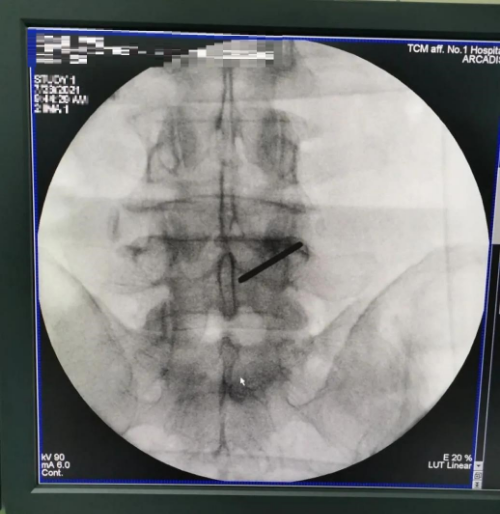

经研讨决定实施治疗:在连续硬膜外麻醉下行经皮后路镜下腰4/5椎间盘摘除神经通道松解术,椎板减压术,纤维环成形术。

术后即刻效果:直腿抬高试验右70度,VAS评分1分。后期仍需按照护理健康宣教进行功能锻炼,及预防下肢深静脉血栓的形成。